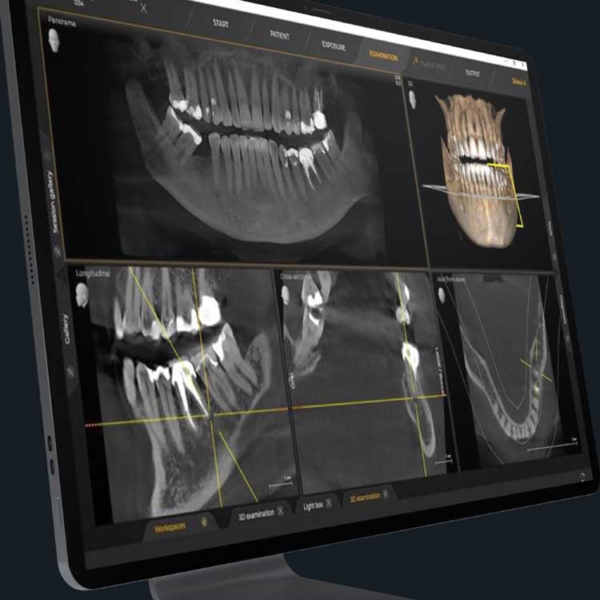

We use the latest titanium files for superior strength and cleaning, and our advanced obturation system ensures the highest level of root canal sealing. Additionally, our clinic is equipped with Cone Beam Computed Tomography (CBCT), allowing us to view your tooth’s roots in 3D, unlike traditional 2D X-rays, for a more accurate diagnosis and treatment plan.